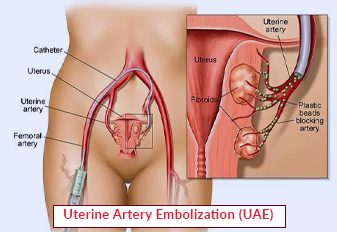

Uterine Artery Embolism: What It Is and Why It’s Crucial for Your Health

When it comes to uterine health, many women face challenges like fibroids and heavy menstrual bleeding. These conditions can significantly impact daily life and overall